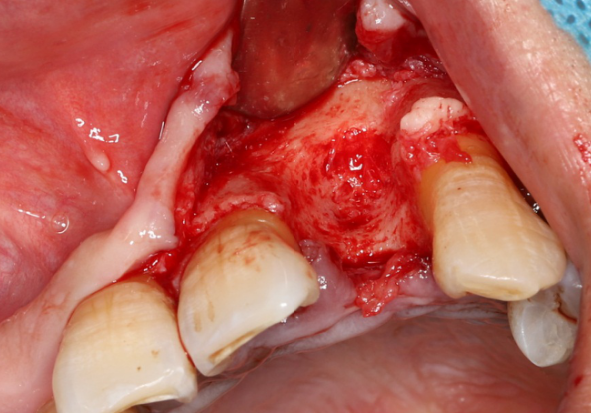

使用12#镰形刀片沿21、22、23做龈沟内切口,于24近中做垂直附加切口。

翻开全厚粘骨膜瓣,暴露22颊侧牙槽骨,微创拔除22。

搔刮22拔牙创,暴露22牙槽骨表面,开放骨髓腔。